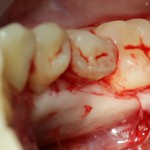

Костная «дверца» на время отделяется и убирается в физраствор, а мы видим следующее:

Это фолликулы и, частично, коронковые части сверхкомплектных зубов.

Теперь аккуратно нам нужно выделить сами зубы:

А вот они! Далее мы руководствуемся главным правилом хирурга-стоматолога: